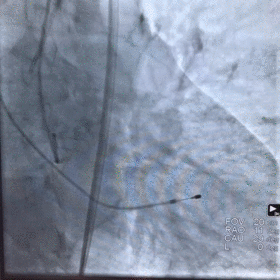

术中影像

图片

根部造影

球囊预扩

释放瓣膜

瓣膜释放至2/3造影观察

瓣膜释放完毕

手术结果

术后造影及超声探查未见瓣周漏,跨瓣压差术前108mmHg,术后几乎无压差,术中及术后未出现相关并发症,手术圆满完成。